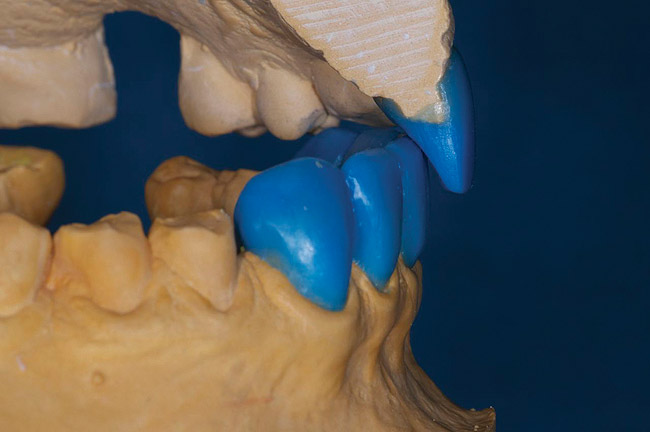

Figure 6  Incisal edge and lingual contour added to the maxillary anteriors.

Figure 6

Figure 7  Length added to the incisal edge of mandibular anteriors and contoured to the proper occlusal plane.

Figure 7